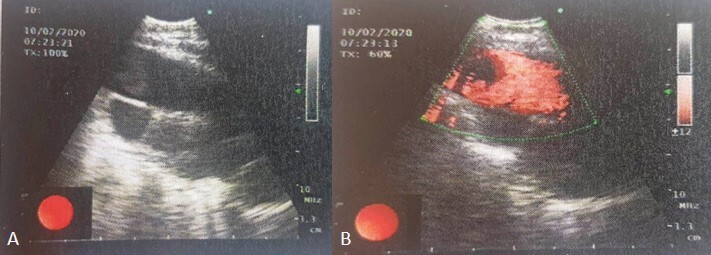

Tuberculosis (TB) is an airborne infectious disease caused by Mycobacterium tuberculosis (MTB). Although it typically affects the lungs (pulmonary TB), one-fifth of TB cases present as extrapulmonary TB. The diagnosis of extrapulmonary TB is often overlooked due to its atypical clinical and radiological manifestations. Differentiating TB from neoplastic conditions poses significant challenges. A 33-year-old female patient was admitted to the emergency clinic with shortness of breath, cough, and abdominal pain. Postero-anterior chest X-ray revealed massive pleural effusion leading to mediastinal shift. With a preliminary diagnosis of malignant pleural effusion, a pleural catheter was inserted, and the patient was referred for a positron emission tomography (PET/CT) to assess the primary site and the optimal location for a biopsy. The PET/CT revealed asymmetric soft tissue thickening on the left side of the nasopharynx, and increased fluorodeoxyglucose (FDG) uptake in the left cervical lymph nodes raised suspicion regarding primary nasopharyngeal cancer. Additionally, there was an increased FDG uptake observed in the mass lesion located in the right upper lobe, mediastinal lymph nodes, pleural surfaces in the left hemithorax, perihepatic areas, and peritoneum, indicating diffuse metastatic disease. Tuberculosis diagnosis was confirmed through biopsies demonstrating granulomatous inflammation in the lung and nasopharynx, along with culturing MTB from pleural effusion. Positron emission tomography played a crucial role in identifying sites of TB involvement. Despite its rarity, healthcare professionals should consider nasopharyngeal TB as a potential diagnosis when evaluating nasopharyngeal masses.